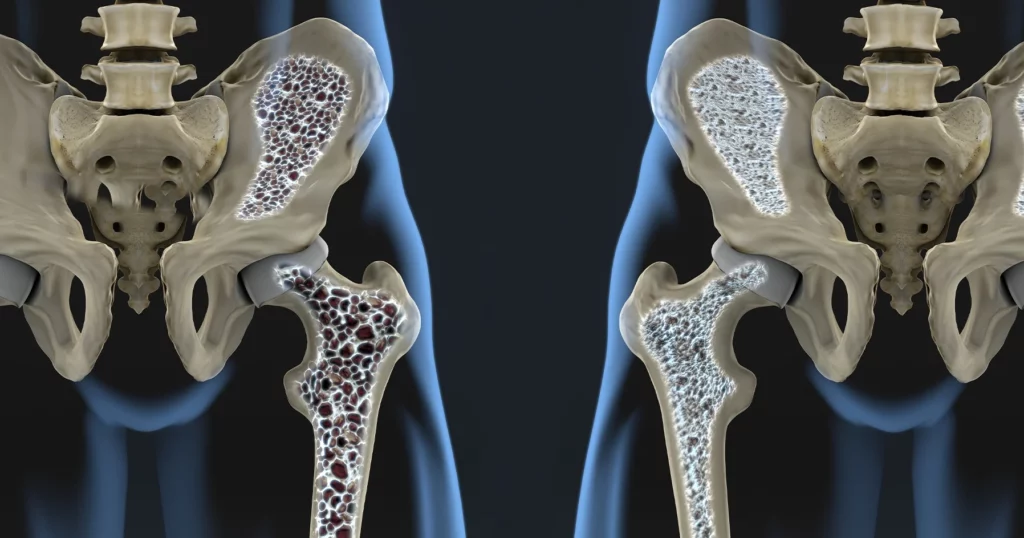

O descoperire majoră în domeniul medical ar putea revoluționa tratamentul osteoporozei, boala care afectează milioane de oameni din întreaga lume. O echipă de cercetători din Germania a identificat un receptor din organism, numit GPR133, care pare să joace un rol crucial în controlul rezistenței osoase. Activarea acestui receptor a dus, în experimente pe animale, la rezultate promițătoare, deschizând noi perspective în lupta împotriva acestei afecțiuni.

Cercetătorii au descoperit că receptorul GPR133, până acum relativ necunoscut, este implicat direct în procesul de formare și menținere a densității osoase. Prin activarea acestui receptor, echipa de experți a reușit să stimuleze creșterea densității osoase și să faciliteze refacerea țesutului osos afectat. Aceste rezultate, obținute în cadrul experimentelor pe animale, sugerează că GPR133 ar putea deveni o țintă terapeutică eficientă în tratamentul osteoporozei.

Osteoporoza, caracterizată prin subțierea și fragilizarea oaselor, este o problemă de sănătate publică majoră. Afecțiunea crește riscul de fracturi, afectând calitatea vieții și generând costuri semnificative pentru sistemele de sănătate. Metodele actuale de tratament, deși eficiente în unele cazuri, pot avea efecte secundare și nu sunt întotdeauna la fel de reușite pentru toți pacienții.

Studiile efectuate au arătat că activarea receptorului GPR133 stimulează celulele responsabile de formarea osoasă, osteoblastele, și inhibă celulele care distrug țesutul osos, osteoclastele. Mecanismul exact prin care GPR133 influențează aceste procese este încă în curs de investigare, dar descoperirile inițiale sunt extrem de încurajatoare. Cercetătorii speră să înțeleagă mai bine modul de funcționare al acestui receptor, pentru a putea dezvolta medicamente eficiente și sigure.